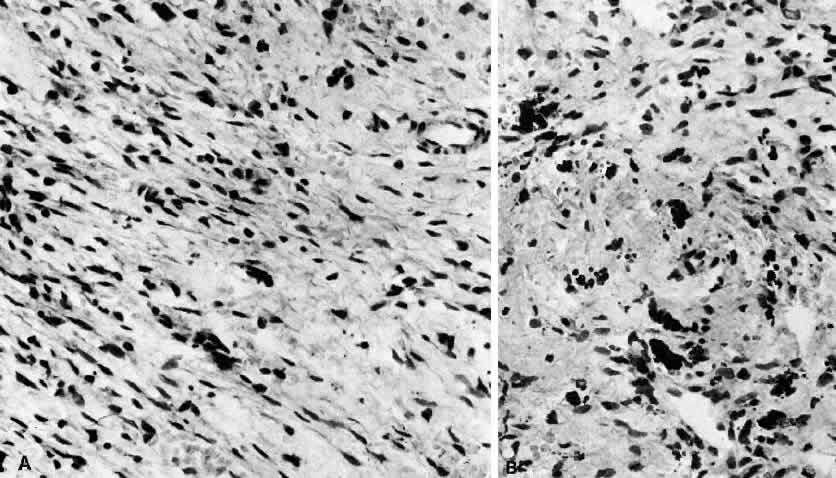

Nodular or pseudosarcomatous fasciitis, while not usually considered part of the spectrum of idiopathic orbital inflammation, represents a localized inflammatory disease of idiopathic origin. It appears to be a reactive process involving a proliferation of immature connective tissue elements along with acute and chronic inflammatory foci (Fig. 7).102–106 This entity has been reported periorbitally in the eyelid as well as in the epibulbar tissue. It may also occur in the anterior or deep orbit. It appears as a rapidly growing mass arising over several weeks or months. It may or may not be associated with pain. At surgery, the lesion appears fairly well demarcated and slightly reddish.

Fig. 7. Fasciitis. A. “Pseudosarcomatous” reactive inflammatory condition is composed predominantly of a loose arrangement of fibroblasts with scattered chronic inflammatory cells (H&E, ×240). B. Conspicuous hemosiderin-laden macrophages are seen in center of photomicrograph. The presence of abundant numbers of capillaries in the inflammatory tissue results in hemorrhage and the presence of blood breakdown products (H&E, ×240).

Histopathology

Microscopically there is a proliferation of immature and active-appearing fibroblasts within the orbital fascial planes.102–106 These fibroblasts may be loosely connected with occasional myxoid foci interposed. Slits often appear between the fibroblasts, which appear to be quite plump and have basophilic cytoplasm. There may be rare mitoses among these cells. Only a minimal amount of collagen deposition is present. The appearance of a gradient from immature fibroblastic elements to more mature fibroblasts is characteristic of this lesion. Also associated with this process is acute and chronic inflammatory cells, capillary and endothelial cell proliferation, and occasional giant cells. Occasionally elements of this inflammatory process can be seen to invade surrounding muscle fibers and orbital fat. The proliferating capillaries are friable and bleed. When this occurs, hemosiderin-laden macrophages can be identified in the tissue. Electron microscopic evaluation of the cells present in this process shows that most are myofibroblasts. These are cells containing rough endoplasmic reticulum and no basement membrane like fibroblasts but also cytoplasmic actin filaments with fusiform densities like smooth muscle cells.3